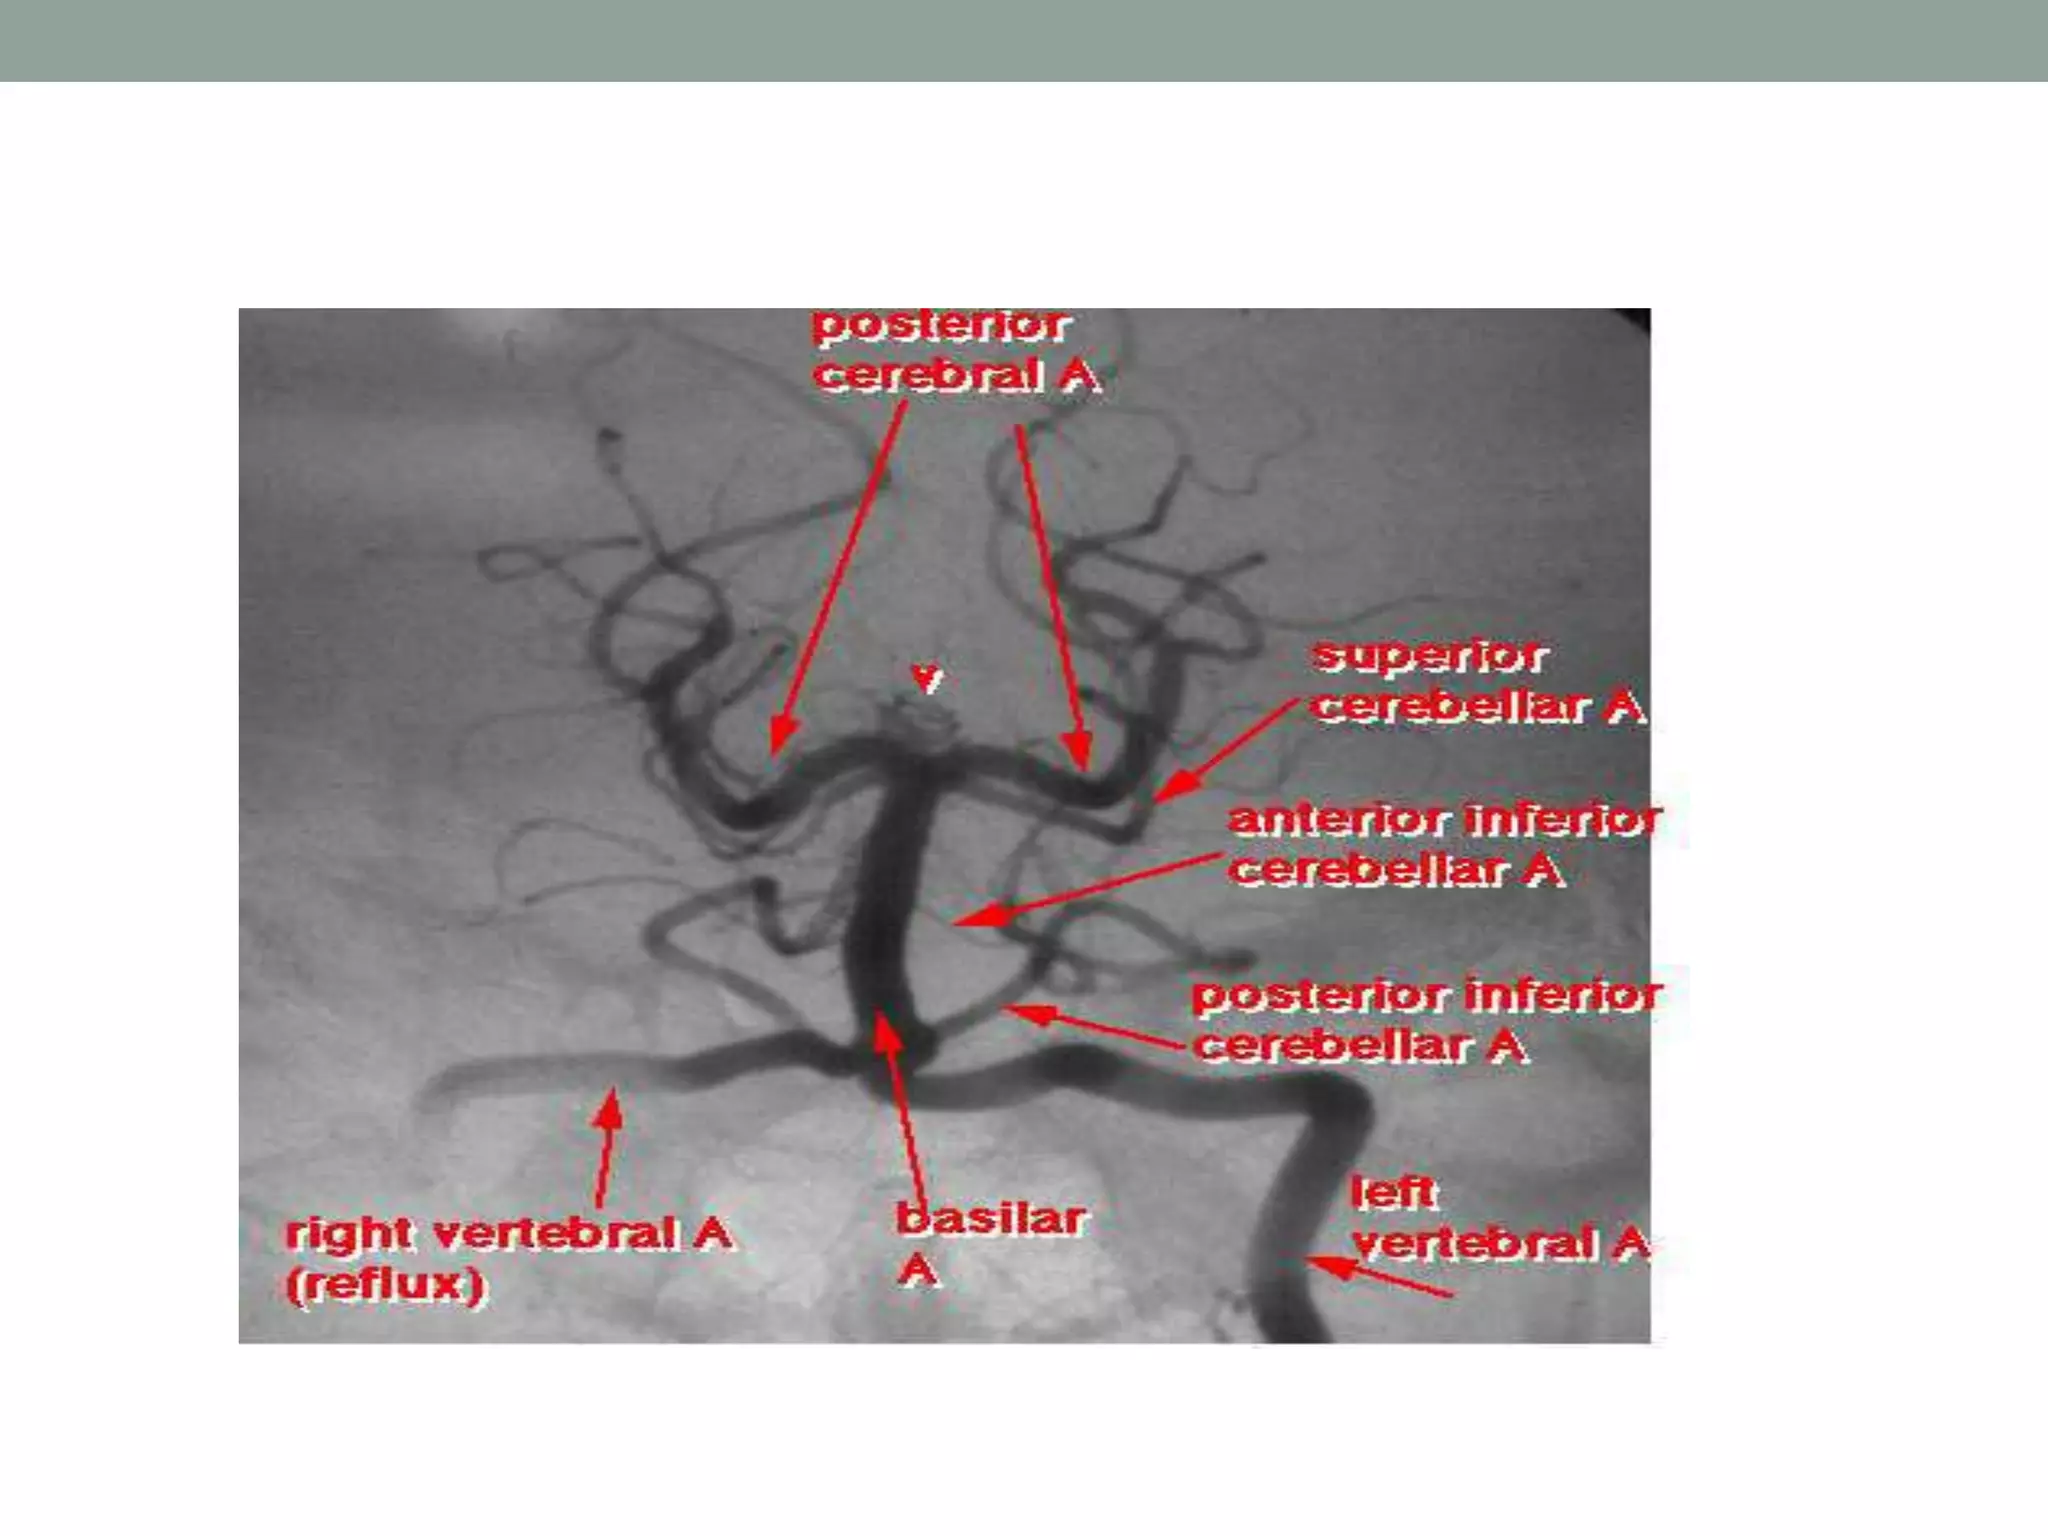

POSTERIOR FOSSA

• Vertebral artery

• Basilar artrery

• Vertebral arteries

• Originate from the subclavian arteries

• Left VA is dominant in 60% cases

Branches of vertebral artery

• Extracranial -numerous branches to the meninges,spinal

cord & muscles

• -Posterior meningeal artery

• Intracranial-

-Anterior spinal artery

• -Posterior inferior cerebellar Art.

• Anterior medullary

• Lateral medullary

• Tonsillomedullary

• Telovelotonsillar

• Cortical branches

BASILAR ARTERY

• Right and left VA unite to form basilar artery

• Courses infront of pons (Prepontine cistern)

terminates in the interpeduncular cistern

• 3cm in length,1.5 to 4mm in width

Branches of basilar artery

• Anterior inferior cerebellar artery (AICA)

• Superior cerebellar artery

• Pontine artery

• Labyrinthine artery

Normal VARIANTS

• Fenestrations and duplications

• Variants of the circle of Willis

• Persistent carotid-basilar anastomoses

• Anomalies identified in the skull base